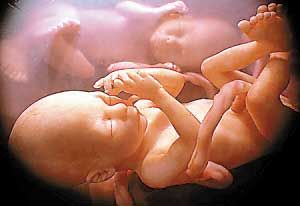

一对双胞胎姐妹中的一个斜靠在另一个身上,还亲了一下对方的脸——这个温馨的画面不是发生在某座大房子里,而是发生在妈妈的子宫里!

这种先进的扫描技术,科学家首次捕捉到之前从未看过的胎儿图像,比如双胞胎和三胞胎在子宫里一边抓着对方的手和脸,一边互相推挤的过程。

由于对胎儿进行的是实时拍摄,科学家把这些珍贵的图像称为“四维”图像,他们按照这些图像制作出真实大小的硅树脂模型,并用电脑制作出令人震惊的多胞胎图像。

从这张清晰的图片中能够看到婴儿脸部的表情的细节,比如微笑和眨眼。亲密举动会影响他们出生后的情感交流。